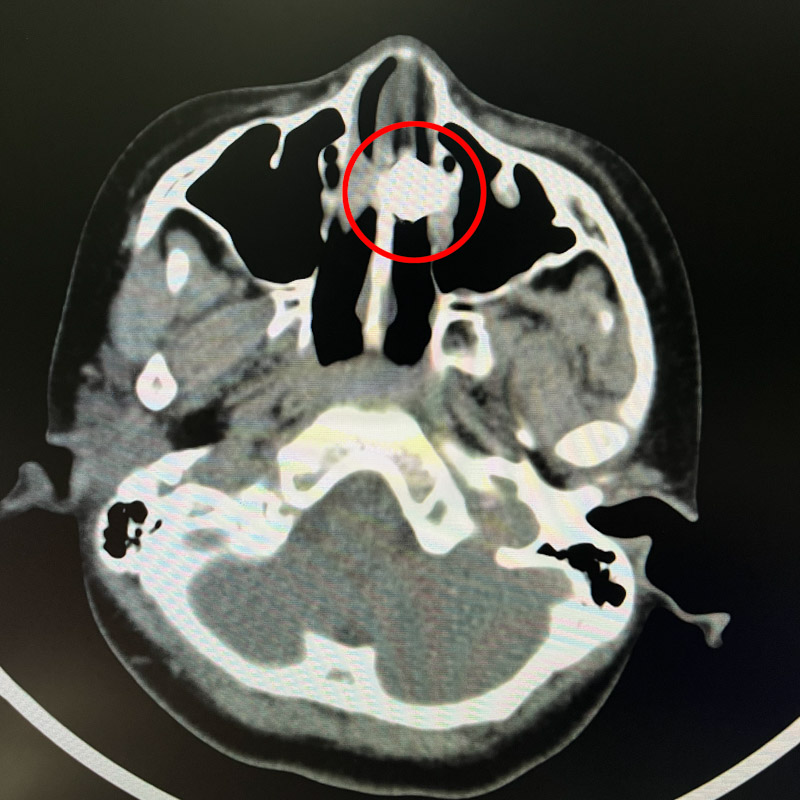

經CT檢查,發現孩子鼻腔內有異物存在,并伴有局部功能受損。耳鼻咽喉科醫生立即安排了急診鼻腔探查手術,術中高清鼻內鏡攝像頭顯示鼻中異物是一枚紐扣電池,而且已經開始腐化,鼻中隔軟骨局部被腐蝕,局部穿孔,左側鼻腔粘連,情況不容樂觀。